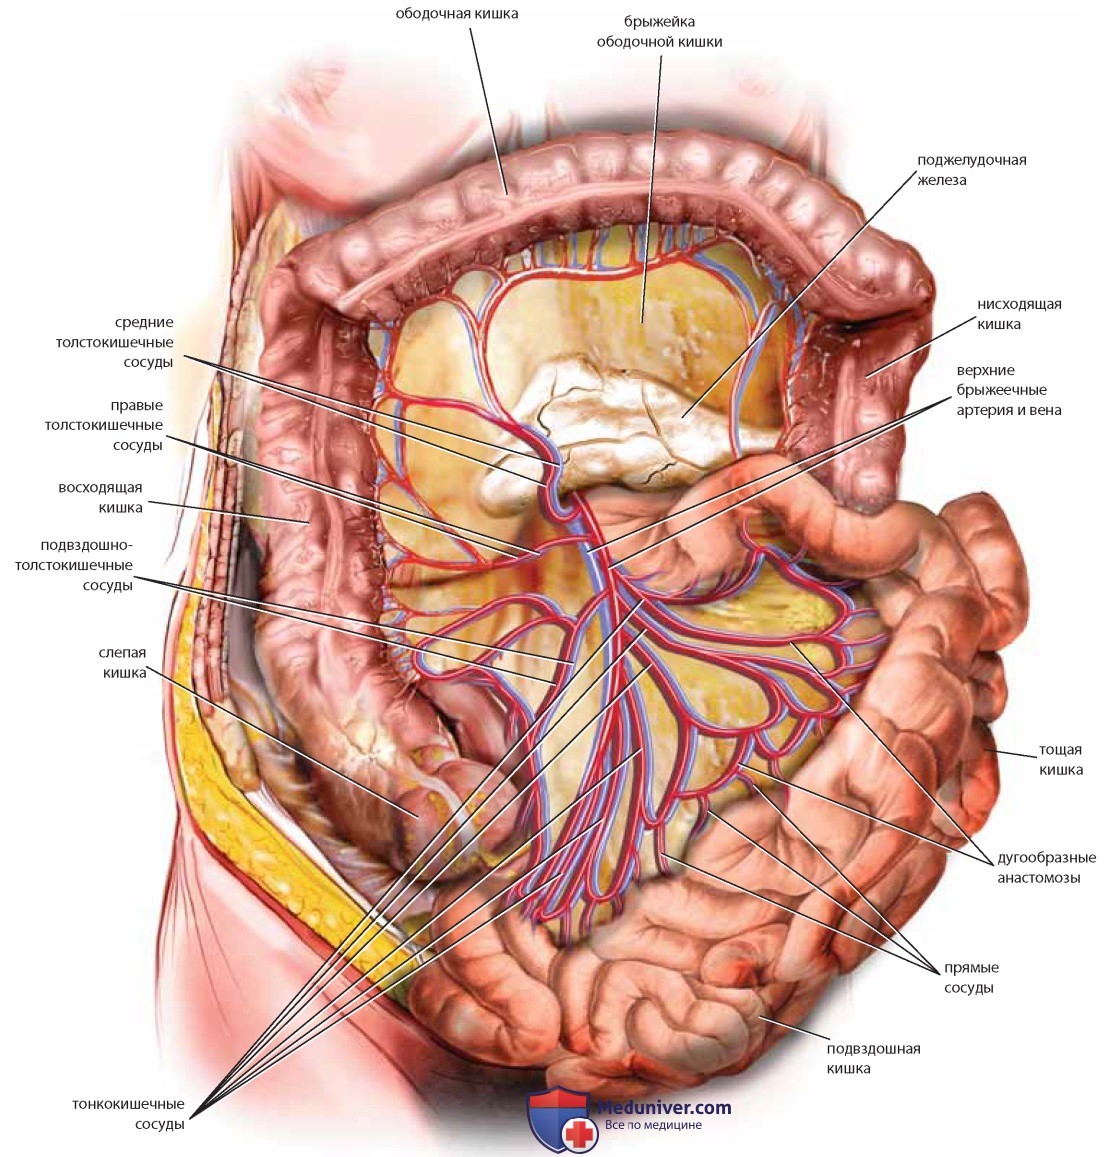

Анатомия малого таза: детальные схемы и изображения

Раздел: Образы вокруг